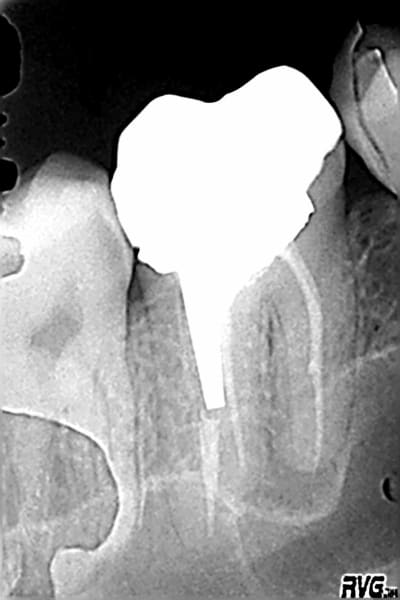

le nombre de fois où le CBCT nous montre des lésion interradiculaires non visibles sur les rétros ...

Ci-joint sur une reprise de traitement, où le cone Beam révélait une fenêtre vestibulaire et un plancher absent, et un mv2 absent.